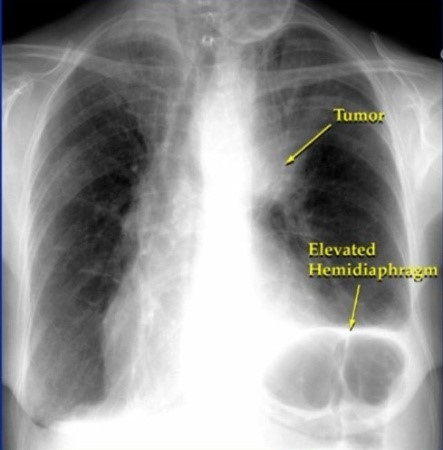

폐암은 위암, 갑상선암 다음으로 3번째로 발병 빈도가 높은 3대 암 중 한 가지인데요. 폐암은 재발과 전이까지의 빈도도 잦은지라 완치가 어렵다고 하며 폐암 발병 초기에는 거의 증상이 없을 수가 있어 수술이 불가능한 3기, 혹은 4기에 주로 진단된다고 해요.

폐암 초기증상 폐암 4기에 이르게 되면 5년 생존률이 30% 대로 감소하게 된다고 해요. 그리하여 폐암은 암 질병이자 중 사망자 비율이 가장 높은 것으로 나타나고 있어요.